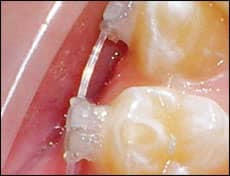

- We placed a metal closed coil around the BioMers wire either in-between the molar and second premolar or the two premolars (Figure 2). The metal coil could also be used to prevent breakage when large unsupported spans of wire lengths are present, but this proved less effective because the metal coils cannot be placed into the bracket slots (unlike the plastic tube). Hence, using the plastic tube is our preference for spans greater than a tooth width. The metal coils are possibly more hygienic than the plastic tubes, so we use them in the shorter interbracket premolar areas when we have areas of wire crazing or fracture.

![]() |

| Figure 2: Metal closed coil was used over a 30-day period, demonstrating that the integrity of the wire was maintained. |